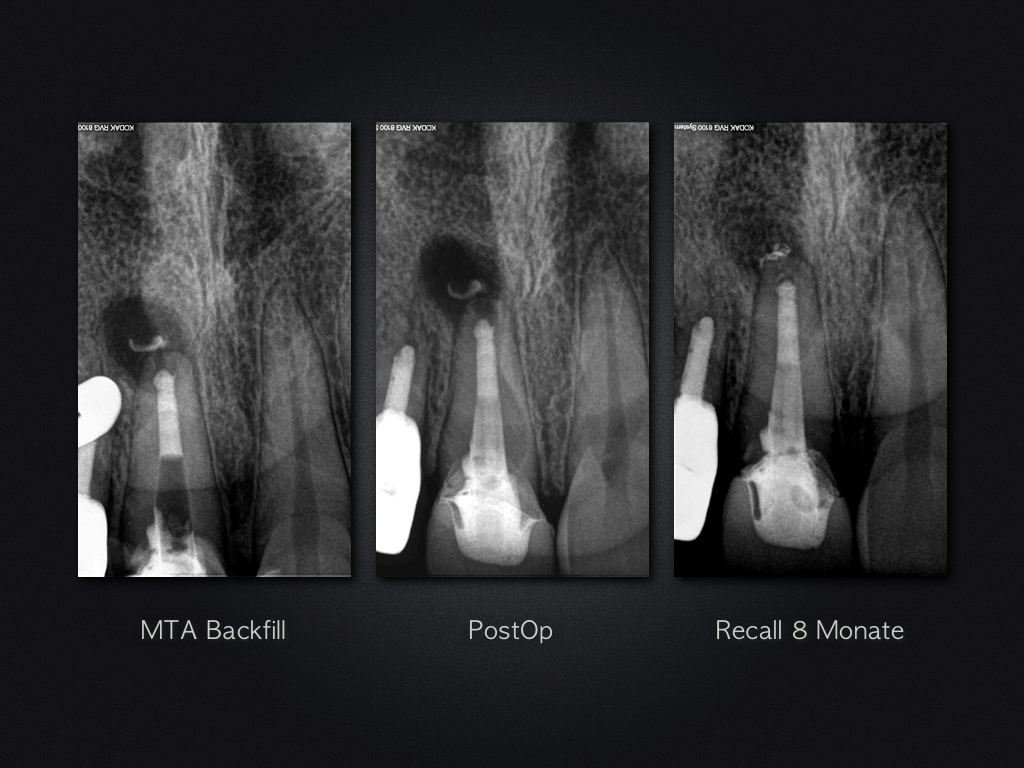

Und es heilt doch!